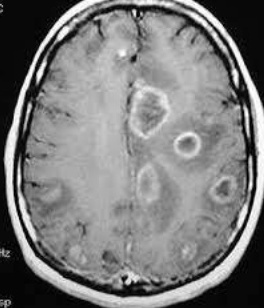

PML: JC virus causes Progressive Multifocal Leukoencephalopathy (PML)

senator count 200 and cane: JC virus reactivated in HIV positive patients with CD4 count <200

white crown leaves: Non-enhancing multifocal brain lesions in white matter (toxoplasma: ring enhancing lesions)

white leaves: white matter affected

peeling legs of table: Leukoencephalopathy is a demyelinating process

pts die in a few months

Nonenhancing:

Enhancing: